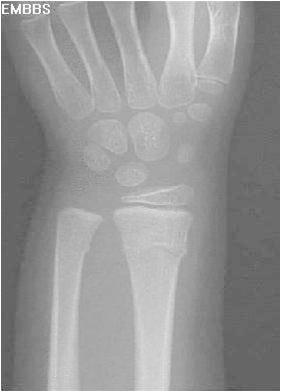

Imaging

• Radiographs

• recommended views

• AP and lateral of wrist

• AP and lateral of forearm

• AP and lateral of elbow if tender about elbow, or diaphyseal fractures present

• findings

• in addition to fracture must evaluate for associated injuries

• scapholunate interval

• DRUJ (distal radio-ulnar joint)

• ulnar styloid

• elbow injuries